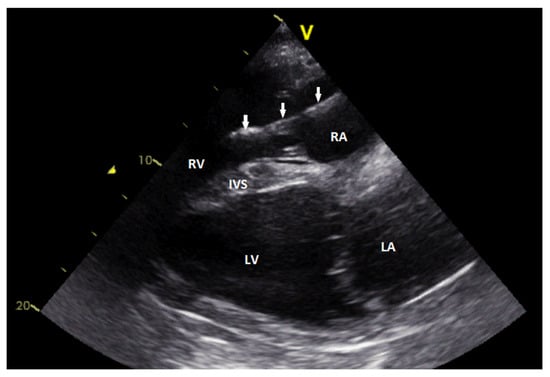

2.2. Electrocardiography and Cardiac Ultrasound